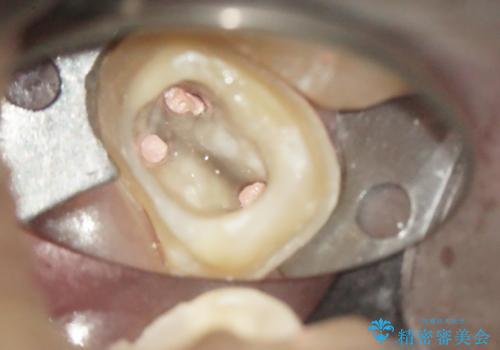

奥歯が感染をおこし強い痛みを出してしまっていたため、顕微鏡を用いた根管治療をおこない根管内を洗浄した後かぶせ物を製作しました。

ひとつひとつの治療を丁寧に行うことで今後も長く使う事ができます。